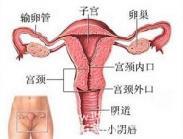

子宫颈平滑肌瘤

628健康网为您分享有关子宫颈平滑肌瘤的症状,子宫颈平滑肌瘤的治疗方法,子宫颈平滑肌瘤的预防知识,子宫颈平滑肌瘤的症状...

宫颈湿疣

628健康网为您分享有关宫颈湿疣的症状,宫颈湿疣的治疗方法,宫颈湿疣的预防知识,宫颈湿疣的症状图片,宫颈湿疣吃什么药,宫...

子宫颈残端癌

628健康网为您分享有关子宫颈残端癌的症状,子宫颈残端癌的治疗方法,子宫颈残端癌的预防知识,子宫颈残端癌的症状图片,子...

子宫癌

628健康网为您分享有关子宫癌的症状,子宫癌的治疗方法,子宫癌的预防知识,子宫癌的症状图片,子宫癌吃什么药,子宫癌怎么治...

输卵管粘连

628健康网为您分享有关输卵管粘连的症状,输卵管粘连的治疗方法,输卵管粘连的预防知识,输卵管粘连的症状图片,输卵管粘连...

输卵管囊肿

628健康网为您分享有关输卵管囊肿的症状,输卵管囊肿的治疗方法,输卵管囊肿的预防知识,输卵管囊肿的症状图片,输卵管囊肿...

原发性输卵管癌

628健康网为您分享有关原发性输卵管癌的症状,原发性输卵管癌的治疗方法,原发性输卵管癌的预防知识,原发性输卵管癌的症状...